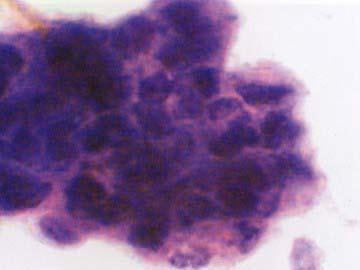

问题 图所示细胞最可能为 ( )

选项 A、正常鳞状上皮细胞 B、正常腺上皮细胞 C、未分化癌 D、分化较好的腺癌 E、分化较好的鳞癌

答案 C